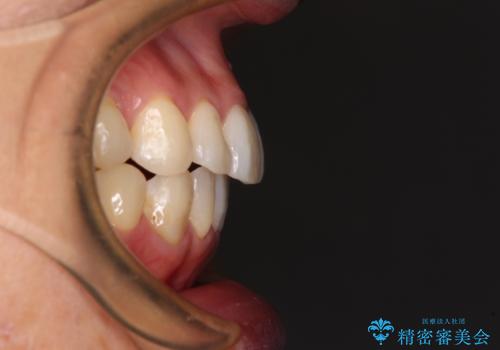

- 捻れた前歯と目立つ銀歯を気にして来院された患者様です。

歯列不正は軽微であったため、インビザライン・ライトにて改善することとしました。

インビザライン・ライトによる矯正治療であったので、時間をかけずに治療を終えることができました。

口を開ける度に目立っていた銀歯もセラミックで自然な口元の印象となりました。